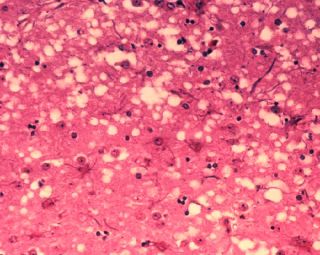

| Microscopic "holes" are characteristic in prion-affected tissue sections, causing the tissue to develop a "spongy" architecture. | |